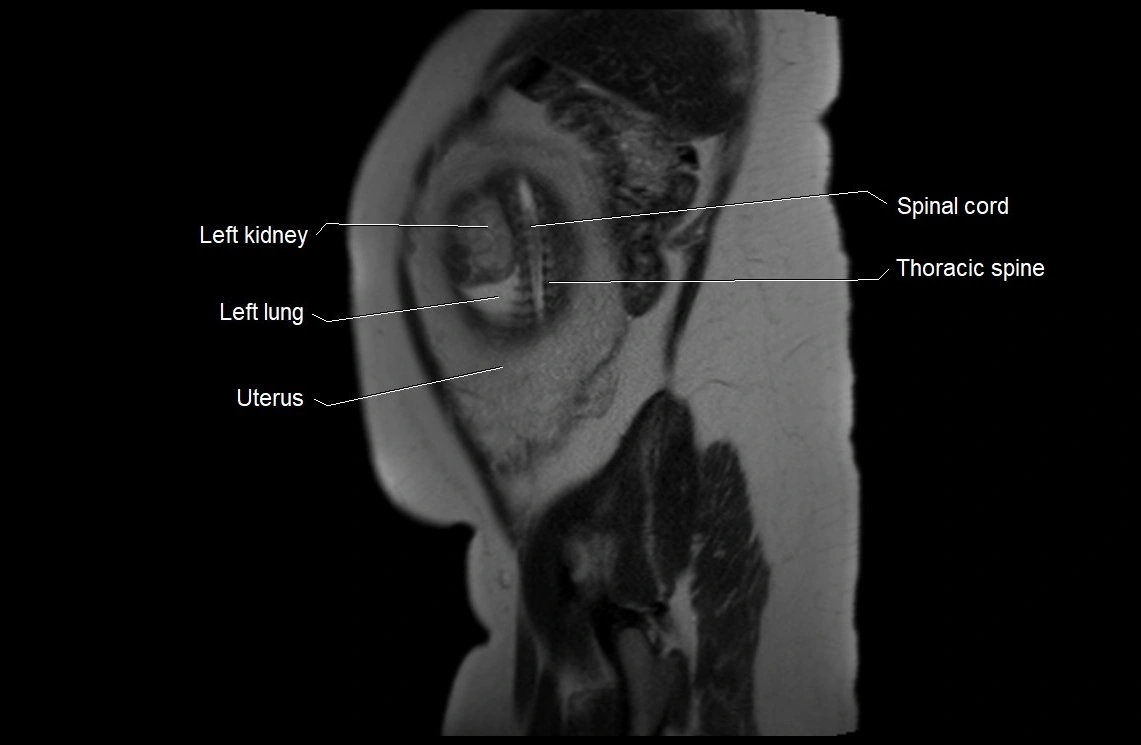

MRI Appearance

T2 HASTE (T2 GRE):

• Amniotic fluid shows very bright hyperintense signal

• Provides natural contrast against fetus and placenta

• Small particles (vernix) may appear as scattered hypointense foci within bright fluid

MRI image

image